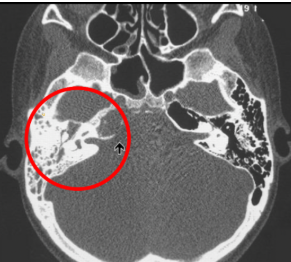

neoplasia del tejido epidérmico que crece en el interior del conducto auditivo, es una complicación de otomastoiditis

19

Q

Qué estudio diagnostica el colesteatoma y cuál es la mejor pista

A

TC Y RM

Pista: Masa que destruye el hueso

Enfermedad que con la secuencia en T2 tipo DWi se muesta una lesión hipertensa